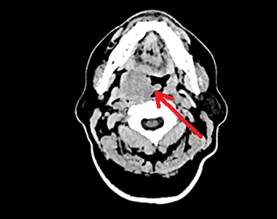

Сравнительный анализ исходного иммунного статуса пациентов продемонстрировал выраженные различия в субпопуляционном составе лейкоцитов периферической крови (рис.2). У пациента с благоприятным клиническим исходом отмечалось повышение абсолютного и относительного содержания лимфоцитов, CD4⁺-клеток, NK- и NKT-клеток, а также T-регуляторных клеток и моноцитов. В то же время у пациента с неблагоприятным исходом преобладали гранулоциты и цитотоксические CD8⁺-клетки.

Выявленные различия могут отражать особенности формирования противоопухолевого иммунного ответа у пациентов с различным клиническим исходом заболевания. Преобладание гранулоцитов и функционально истощенных CD8⁺-клеток у пациента с неблагоприятным исходом может указывать на дисбаланс иммунной регуляции. Накопление гранулоцитарного звена и истощенных CD8⁺-клеток ассоциировано с формированием иммуносупрессивного опухолевого микроокружения, снижением эффективности противоопухолевого иммунного контроля и прогрессированием заболевания, что продемонстрировано, в частности, для ДВКЛ [12]. Аналогично CD8⁺-лимфоцитам, NK-клетки в опухолевом микроокружении могут приобретать истощенный фенотип, что сопровождается снижением их цитотоксической активности и способствует иммунному уклонению опухоли [13]. Напротив, повышенное содержание CD4⁺-клеток, а также сохранность функциональной активности NK- и NKT-клеток, вероятно, отражают более сбалансированное взаимодействие врожденного и адаптивного звеньев иммунной системы и ассоциированы с более эффективным противоопухолевым иммунным надзором [14].

Рис.2. Инициальный иммунофенотип клеток периферической крови пациентов с ДВКЛ. Лф – лимфоциты, мон – моноциты, гран – гранулоциты, Т-реr – Т-регуляторные клетки.

Примечание: составлен авторами по результатам данного исследования

Выявленные иммунофенотипические различия, в частности более высокое содержание NK-клеток и соотношение CD4+/CD8+-лимфоцитов у пациента с благоприятным прогнозом, согласуются с литературными данными о важности клеточного иммунитета в контроле над опухолевым ростом при лимфопролиферативных заболеваниях [17, 18].